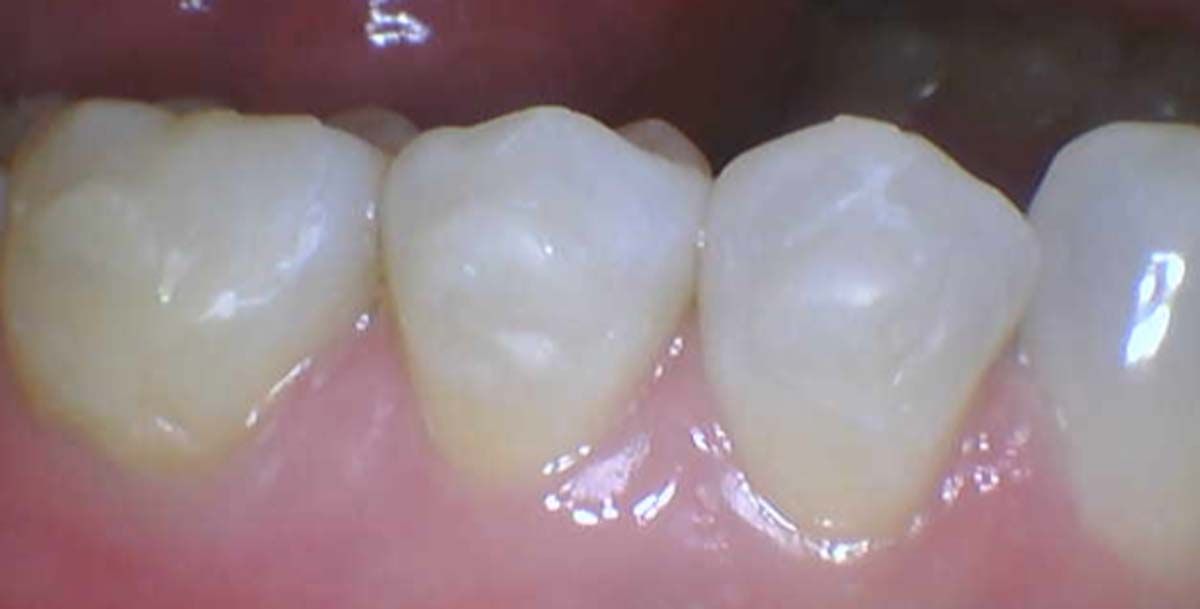

We used to try showing patients their clinical situation on 2D x-rays and demonstrating treatment using models. Later, digital intraoral cameras helped, but they could not show much more than what a patient could see in a mirror. Today, it is possible to show patients every angle of their clinical situation in hyperrealistic 3D with a CBCT scan. Now, when I recommend treatment to patients and they ask why, I am armed with an interactive image captured by my CS 8200 3D extraoral imaging system (Carestream Dental). I scroll through the tooth and bone, point out lesions below the surface, and show why there is or is not enough bone for an implant. If you use something like the Prosthetic-Driven Implant Planning module to automatically merge an intraoral scanner file with the CBCT scan, you create an even more accurate picture. How much easier is it for the patient to accept treatment when they are seeing the end results of that treatment?